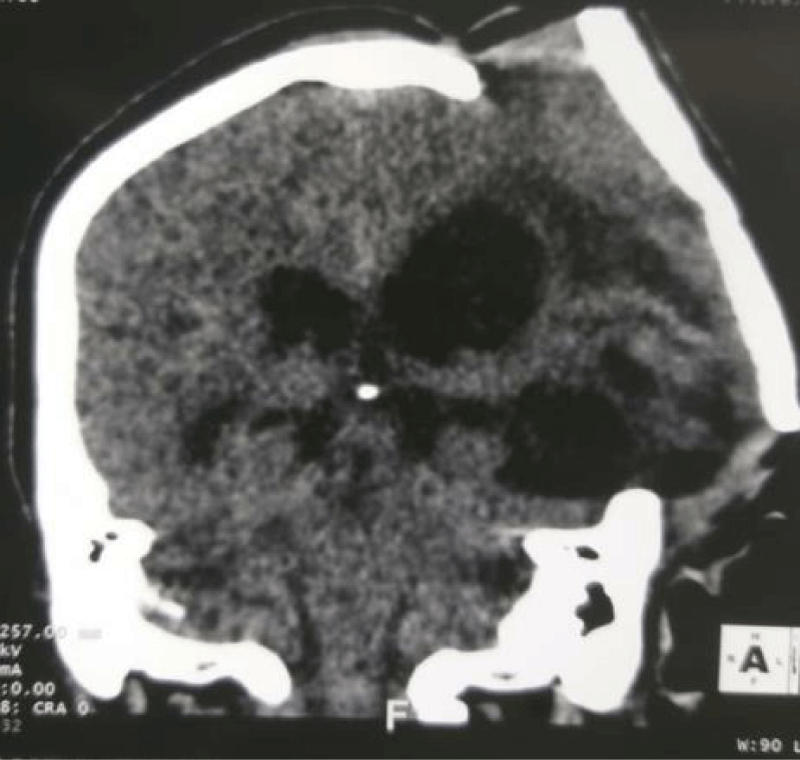

The patient is 57 years old, male, with no specific history admitted to the emergency room for severe head trauma by road accident. At the clinical examination he presented altered consciousness, Glasgow Coma Scale 7 (E1 V1 M5) with right hemibody deficit. Brain CT revealed an acute left hemispherical subdural hematoma with a significant shift. A left hemispherical decompressive craniectomy was performed urgently to control intracranial hypertension. There was significant clinical improvement and the patient discharged from hospitalization after a few days. A left hemispherical cranioplasty was performed after 3 months using surgical cement. Two months after cranioplasty, the patient is readmitted to hospital for convulsive seizures of the right half of the body. Glasgow at 8 (E4V1M3), anisocoria with photo reactive left mydriasis and cranioplasty uplift (Figure 1). Brain CT showed hydrocephalus, loss of fixation of the cranioplasty flap with expansion of the brain parenchyma out of the cranial box (Figure 2). An External Ventricular Drainage (EVD) was placed urgently with clinical improvement with regaining of consciousness and arrest of seizures. A Ventriculoperitoneal Shunt (VPS) was placed afterwards (Figure 3) and the patient discharged from hospitalization after a few days (Figure 4). We didn’t fix the cranioplasty after the ventriculoperitoneal shunt. Nevertheless we plan to replace the cranioplasty flap by an other and fix it.